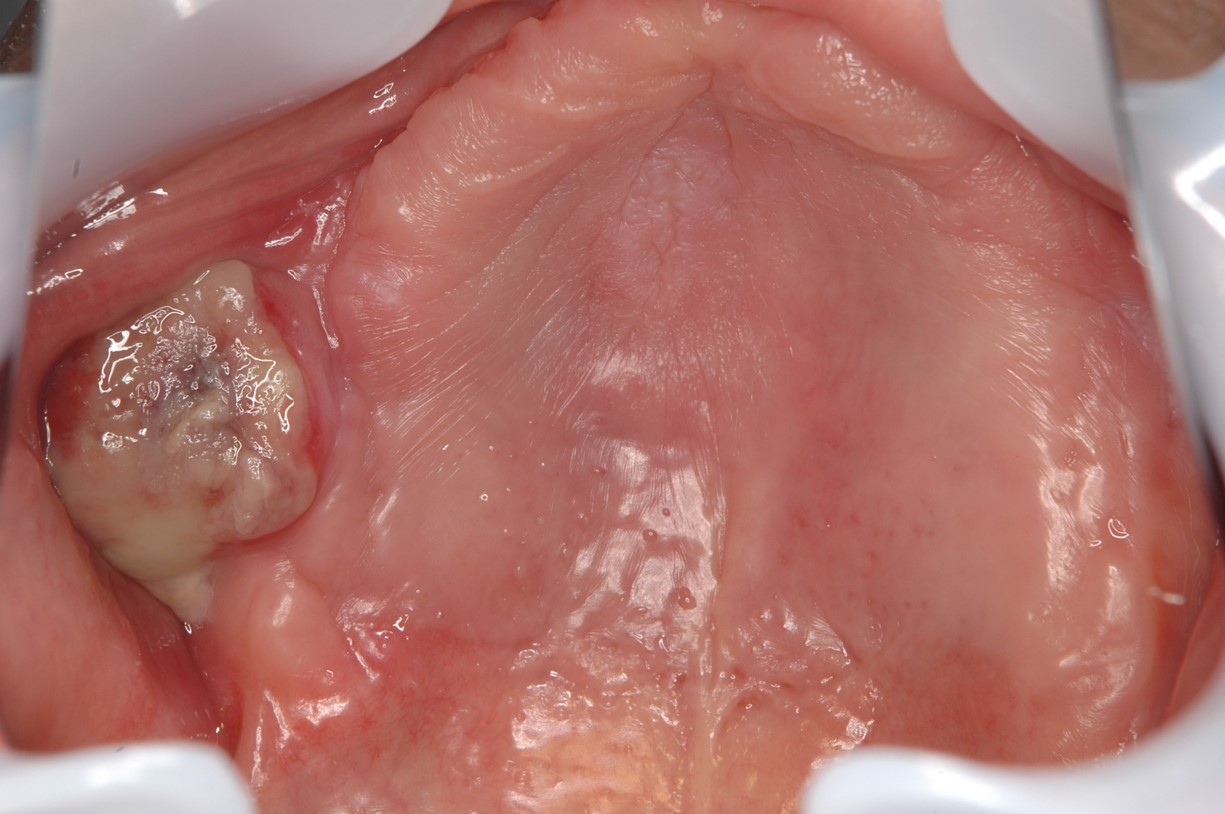

原因不明の歯のぐらつきが3週間以上続いている

抜歯後(歯を抜いた後)、なかなか治らない状態が3週以上続く。

歯肉がんの場合に、がんが歯を支えている骨を吸収することがあります。

ぐらついた歯の周りの歯肉が、汚く盛り上がっていたり、上皮に潰瘍やびらんがあれば要注意です。同様に、抜歯した後、3週間以上経っても、なかなか治らない場合も要注意です。